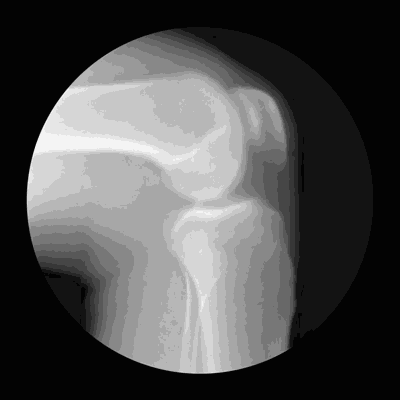

腰酸背痛、蹲下站不起、关节“咔咔”响、身高变矮、弓腰驼背……上年纪后这些接踵而至的变化,大多与骨骼变老、骨质流失有关。

常言道“人老骨先老”,没有健壮挺拔的“身子骨”,人体这座“大厦”就会面临重重危机。要想骨骼结实,需要补足多种营养。

骨头就像个“钙仓库”,人体99%的钙都储存在骨头和牙齿里,让骨头保持一定的强度和硬度。人的骨骼是“活”的,当钙摄入不足时,骨骼中的钙就会释放到血液里,以维持血钙浓度,导致骨密度越来越低,骨质越来越疏松,进而引发骨折、骨质退行性增生。